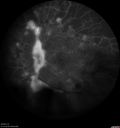

Proliferative Diabetic Retinopathy - NVD regressed with PRP laser377 views76 year old diabetic man - Presented one year ago with NVD in the left eye. This regressed with laser but then a year later worsened. Additional PRP was done and the NVD regressed again.Jun 02, 2017

Proliferative Diabetic Retinopathy - NVD regressed with PRP laser401 views76 year old diabetic man - Presented one year ago with NVD in the left eye. This regressed with laser but then a year later worsened. Additional PRP was done and the NVD regressed again.Jun 02, 2017

Proliferative Diabetic Retinopathy - NVD regressed with PRP laser443 views76 year old diabetic man - Presented one year ago with NVD in the left eye. This regressed with laser but then a year later worsened. Additional PRP was done and the NVD regressed again.Jun 02, 2017